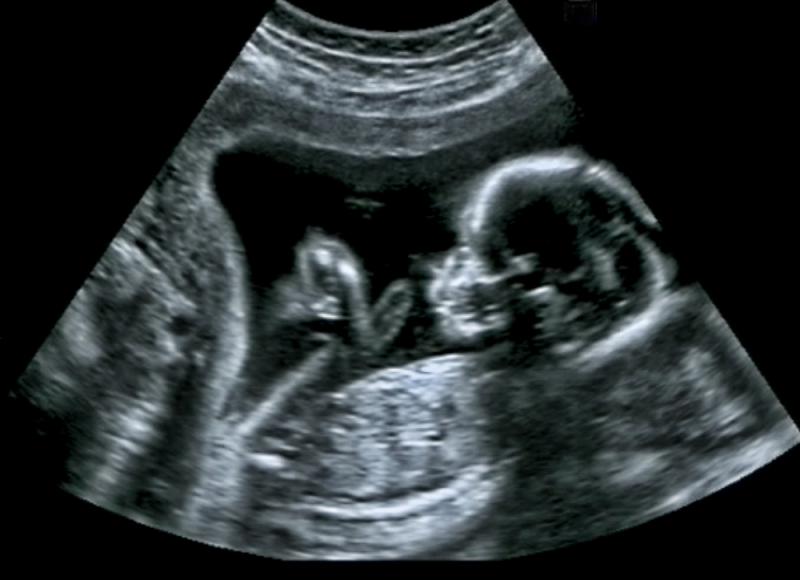

Definitywne rozpoznanie ciąży możliwe jest dzięki stwierdzeniu tzw. pewnych objawów ciąży, do których zalicza się wysłuchanie czynności serca płodu, palpacyjne wyczucie części ciała bądź ruchów płodu w macicy, graficzny zapis tonów (fonokardiografia płodowa) bądź prądów czynnościowych serca (elektrokardiografia płodowa) oraz wizualizację pęcherzyka ciążowego w jamie macicy (ultrasonografia).

Pierwszy trymestr ciąży, trwający od pierwszego dnia ostatniego cyklu menstruacyjnego do 13 tygodnia ciąży, stanowi najważniejszy okres organogenezy. Proces ten rozpoczyna się od połączenia się komórki jajowej z plemnikiem w jajowodzie. Powstała w ten sposób zygota rozpoczyna cykl podziałów mitotycznych (bruzdkowanie) wraz z wędrówką wzdłuż jajowodu w kierunku macicy. Dzieląca się zygota dociera do macicy w stadium moruli i przez 2-4 dni przebywa w jamie macicy odżywiając się wydzieliną błony śluzowej macicy (tzw. mleczkiem macicznym). Morula przekształca się w tym okresie w blastocystę, która po upływie tygodnia od zapłodnienia zagnieżdża się w błonie śluzowej macicy. Struktura ta różnicuje się następnie na wewnętrzny embrioblast (węzeł zarodkowy) dający początek trzem listkom zarodkowym, z których rozwiną się wszystkie komórki, tkanki i narządy organizmu; i zewnętrzny trofoblast (kosmówkę), która wraz z błoną śluzową macicy tworzy łożysko – odpowiedzialne za ochronę mechaniczną, dostarczanie substancji odżywczych, wymianę gazową, usuwanie produktów przemiany materii zarodka i produkcję hormonów podtrzymujących ciążę (progesteronu). Powstają pierwotne narządy osiowe, m.in. struna grzbietowa (zastępowana przez kręgosłup) oraz cewka nerwowa (przekształcające się w mózg i rdzeń kręgowy); rozwijają się narządy ostateczne (m.in. serce, mózgowie, rdzeń kręgowy, płuca, narządy układu pokarmowego, mięśnie, kończyny). Z początkiem trzeciego miesiąca ciąży rozpoczyna się okres płodowy; zarodek określany jest odtąd mianem płodu. Pod koniec pierwszego trymestru płód osiąga ok. 50 mm długości i ciężar ok. 14 g; wykazuje proste odruchy i zdolność poruszania się.